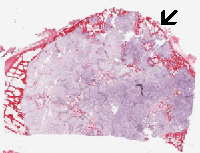

On the histologic slide, this tumor is composed of a low-grade

neoplastic chondroid of low cellularity. The overall cytologic

features are reminiscent of normal cartilage but they are separated

into numerous lobules separated by thin fibrovascular bands.

These lobules can vary from one to several millimeters in diameter.

The tumor bulge out and disrupted the cortical bone.

-

In another location of the tumor, there is definitive

invasion

of the haversian system. This is an important features for the

diagnosis of chondrosarcoma.

Diagnostic wisdom: Demonstration of invasion of the

haversian system and/or the Volkmann's canal are mostly seen

at the periphery where the tumor interface with the bone. However,

this amount of tissue from this location may be limited and rather

fragmented in biopsy material particularly core biopsy. Careful

examination of the available material and correlation with

radiographic findings are the two keys for correct diagnosis.